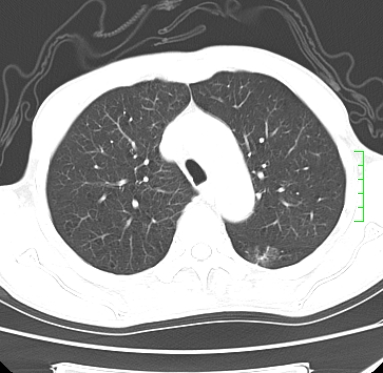

m,73y。膝关节疼痛伴双下肢水肿。入院常规胸片发现结节灶。增强为静脉期。

浅分叶、棘突,考虑右下肺周围型肺癌

考虑周围型肺癌  ,双上肺结核。

肿块周围可见局限性气肿,考虑肺癌可能性大。双肺上叶继发型肺结核。

指套征,强化明显,近侧肺组织局限性肺气肿,考虑支气管类癌,慢支、肺气肿、双上陈旧性tb、冠脉钙化。

鉴别:先天性支气管闭锁,变态反应性支气管肺曲霉菌病,肺癌,支气管囊肿,支扩黏液嵌塞。

1)考虑右肺下叶周围型肺癌。2)右肺上叶及左肺感染性病变(结核可能)。3)肺气肿。4)冠状动脉钙化。